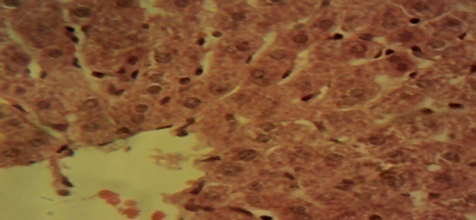

Compared to rats in the control and in the therapeutic dose groups, that showed normal hepatic lobules composed of normal hepatocytes arranged in interconnecting cords around the central vein in their histo-architecture (Figure 1 & Figure 2), mild to moderate changes including hepatocellular necrosis observed in the liver sections of the other groups (Figure 3–5) were moderate to severe in the group of rats exposed to overdose of AL together with MSG (Figure 6).

Figure 2 Photomicrograph of the liver of the therapeutic dose animal showing normal hepatic histomorphology for laboratory rodents (×400).

Figure 3 Photomicrograph of the liver of the overdose animal showing multifocal areas of hepatocellular necrosis (×400).